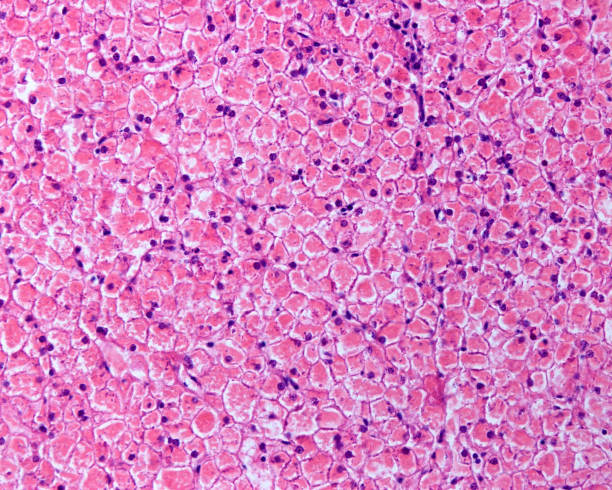

Der Glykogenkörper (Corpus gelatinosum) ist eine Sonderbildung im Bereich des Rückenmarks bei Vögeln. Die gallertige, eiförmige Masse ist eine Ansammlung glykogenreicher Zellen um den Zentralkanal im Bereich der Lendenschwellung (Intumescentia lumbosacralis) des Rückenmarks. Sie reicht rückenwärts bis an die Rückenmarkshäute. Zudem enthält der Glykogenkörper saures Gliafaserprotein und ist vermutlich ein Abkömmling der Astroglia. Die Funktion des Glykogenkörpers ist unbekannt, er ist kein Speicherorgan für Glykogen. Studien zur Enzymausstattung lassen vermuten, dass das Glykogen über den oxidativen Pentosephosphatweg verwertet wird und der Glykogenkörper bei Vogelembryonen bei der Lipid- und Myelin-Synthese im Zentralnervensystem eine Rolle spielt.